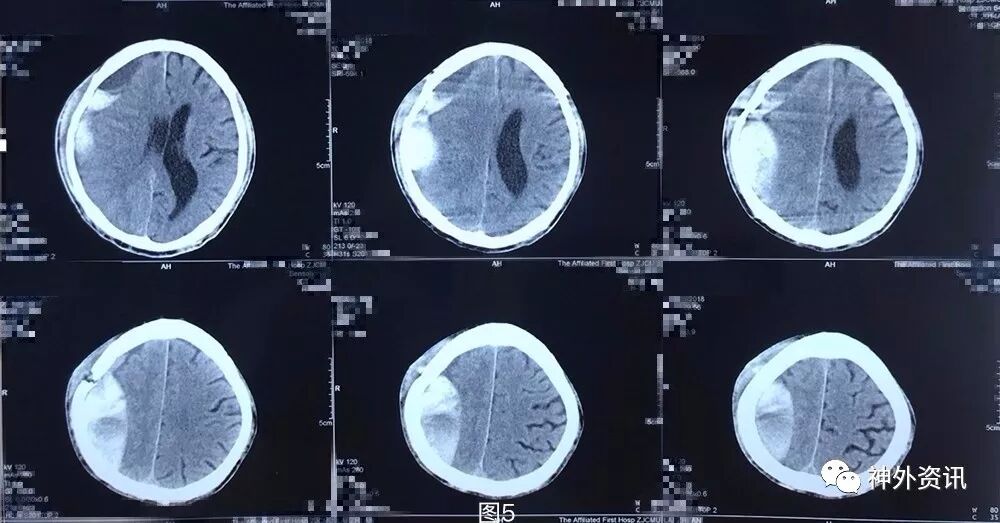

患者5月前不慎头部外伤,当时无黑懵晕厥,无头痛头晕,未重视治疗,3月余前无明显诱因下出现头痛,伴头晕,伴行走不稳,前往外院就诊,查头颅CT示:右侧额颞顶枕部慢性硬膜下血肿考虑(图1),行钻孔引流术。术后复查头颅CT提示右侧额颞顶枕慢性硬膜下血肿钻孔引流术后改变(图2),术后症状好转出院。2月前(术后1月)患者再次出现头痛晕头晕等症状,复查头颅CT:右侧额颞顶枕硬膜下血肿,脑实质受压,中线轻度左偏(图3)。遂再次行右额颞顶枕部硬膜下血肿钻孔引流术,术后患者头痛无明显好转,伴左侧肢体乏力,复查头颅CT见术后局部血肿形成(图4)并进行性增大(图5)。

图5. 第2次手术后4天头颅CT提示:右侧额颞顶枕硬膜下血肿局部血肿继续增大。

图10. 第三次术后第10天,局部积血密度逐渐下降,提示血肿液化可能。